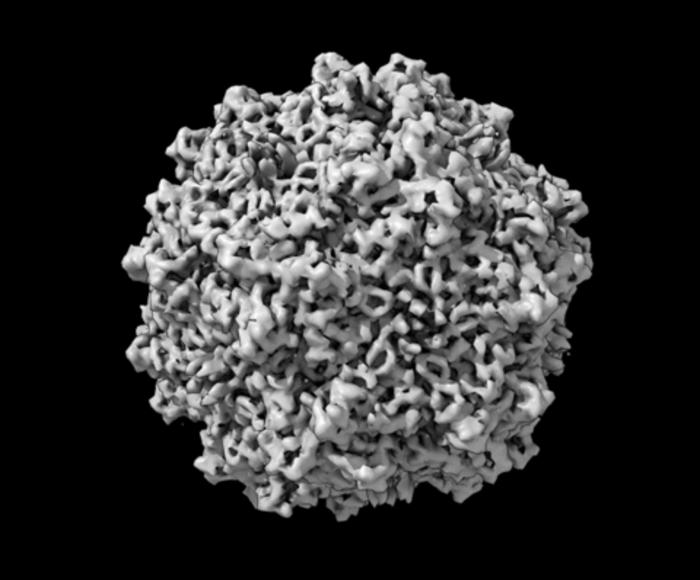

In a landmark study that holds significant implications for the field of gene therapy, researchers have conducted an exhaustive evaluation of widely-used measurement techniques employed in the quantification of adeno-associated viruses (AAVs). These viruses are crucial in the delivery of therapeutic genetic material, allowing for innovative treatments targeting the root causes of genetic disorders and diseases. However, the study has called into question the reliability of one of the most prevalent measurement methods, determining it to be “problematic” and in need of comprehensive refinement and standardization.

AAVs have gained recognition for their utility in gene therapy, since they can be precisely engineered to deliver therapeutic genetic entities into targeted cells. In this process, the harmful viral genetic material is substituted with a therapeutic payload that aims to correct genetic deficiencies or express beneficial traits. The administration of these tailored AAVs to patients, however, necessitates a reliable evaluation of their concentration and efficacy, which hinges on assessing the viral vector’s genetic material and viral particles accurately.

Image Credits: Thomas Cleveland (NIST)